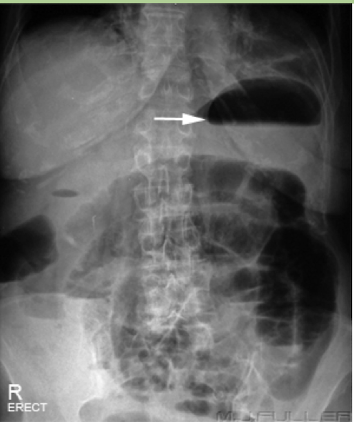

Gastric Bubble

common normal finding

Abdominal Radiograph

Pneumoperitonem

free air under the diaphragm

abnormal finding, perforated until proven otherwise

Abdominal Radiograph

Small bowel obstruction (SBO)

dilation and multiple bubbles, air fluid levels

Abdominal Radiograph

Small bowel obstruction (SBO)

“string of pearls” finding

Abdominal Radiograph